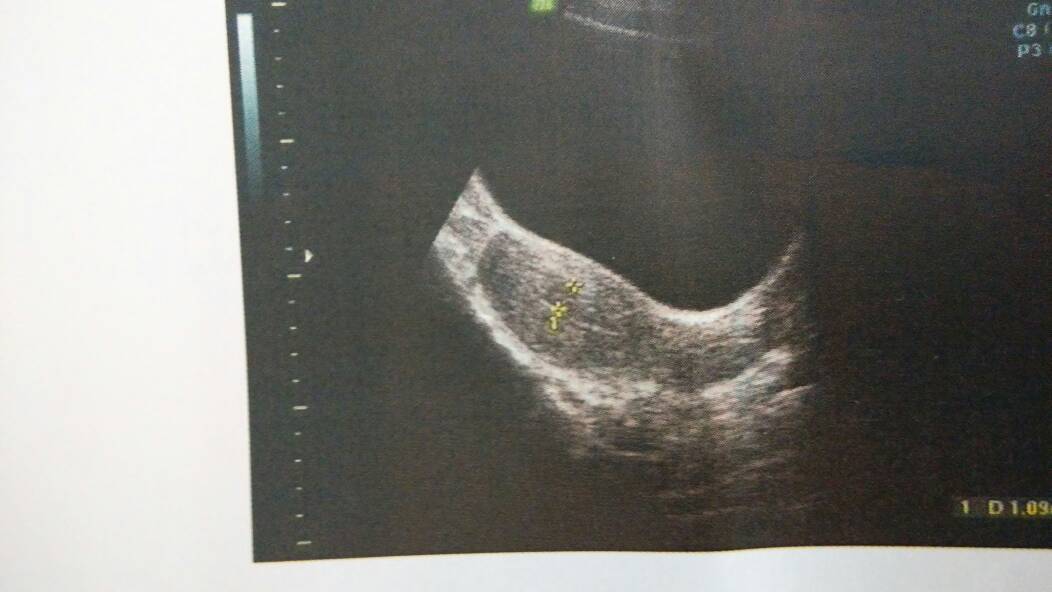

8月30号怀孕14周,因羊水破引产,因为害怕清宫,吃了一周多的益母草和宫血宁,今天去做的彩超,,请医师帮我看看,严重不?

你这属于刮宫了...胚胎组织残留这么久早就坏死。不过首次刮,影响也不大,弄完后月子还是要坐的。不要老是蹲着,也不要吃辛辣刺激的,烟酒。二手烟也要拒吸。年轻人很容易恢复的。